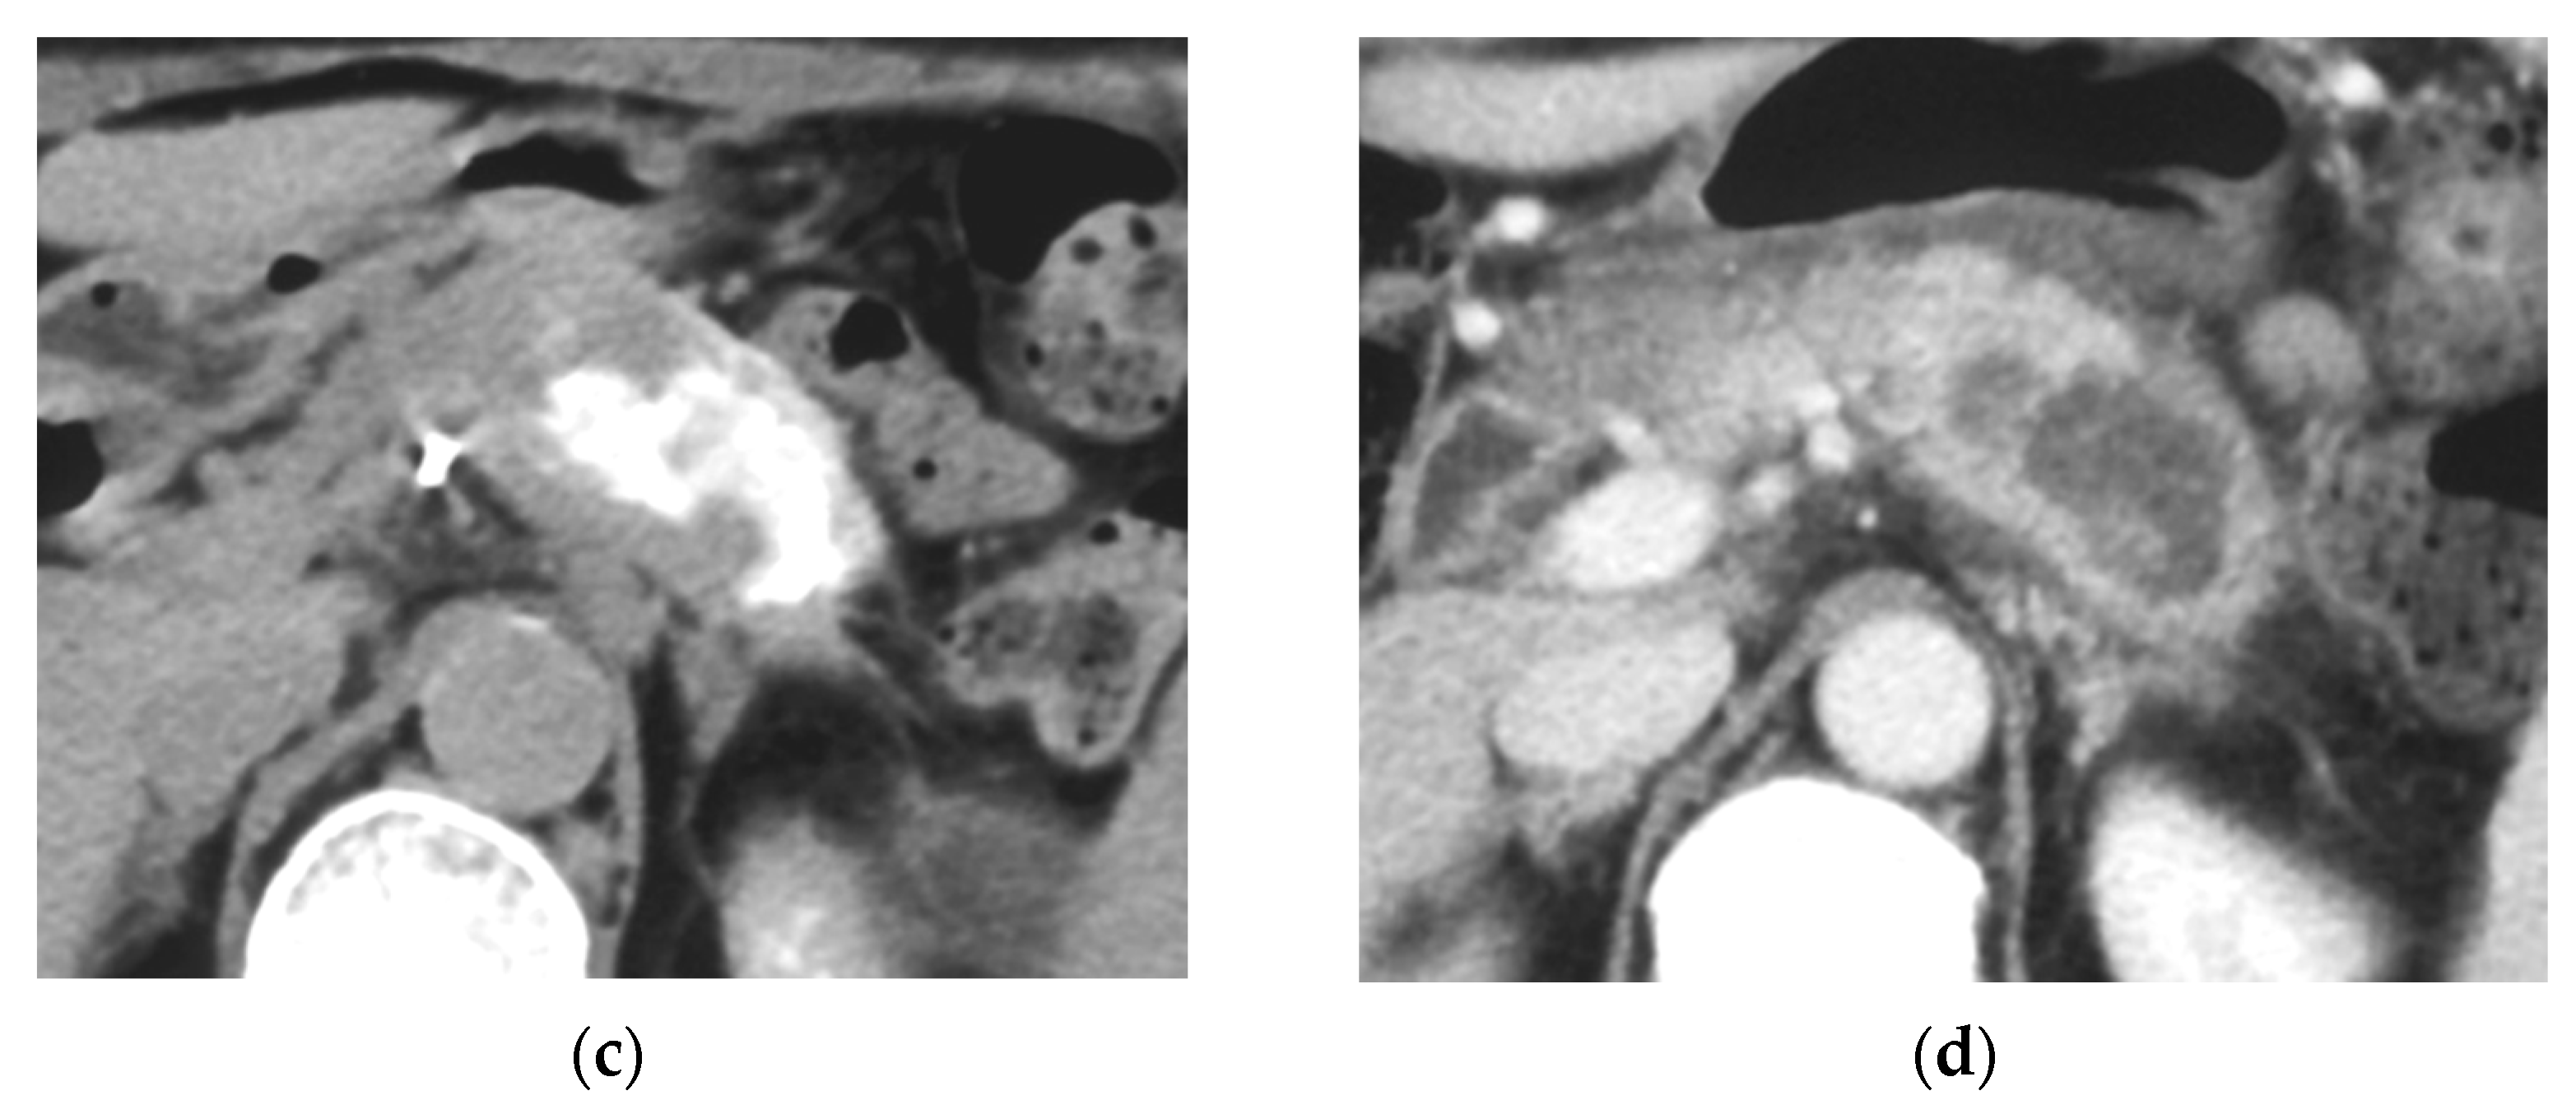

Identifying Supplying Arteries to Pancreatic Cancer

Method of Arterial Administration of Anticancer Agents